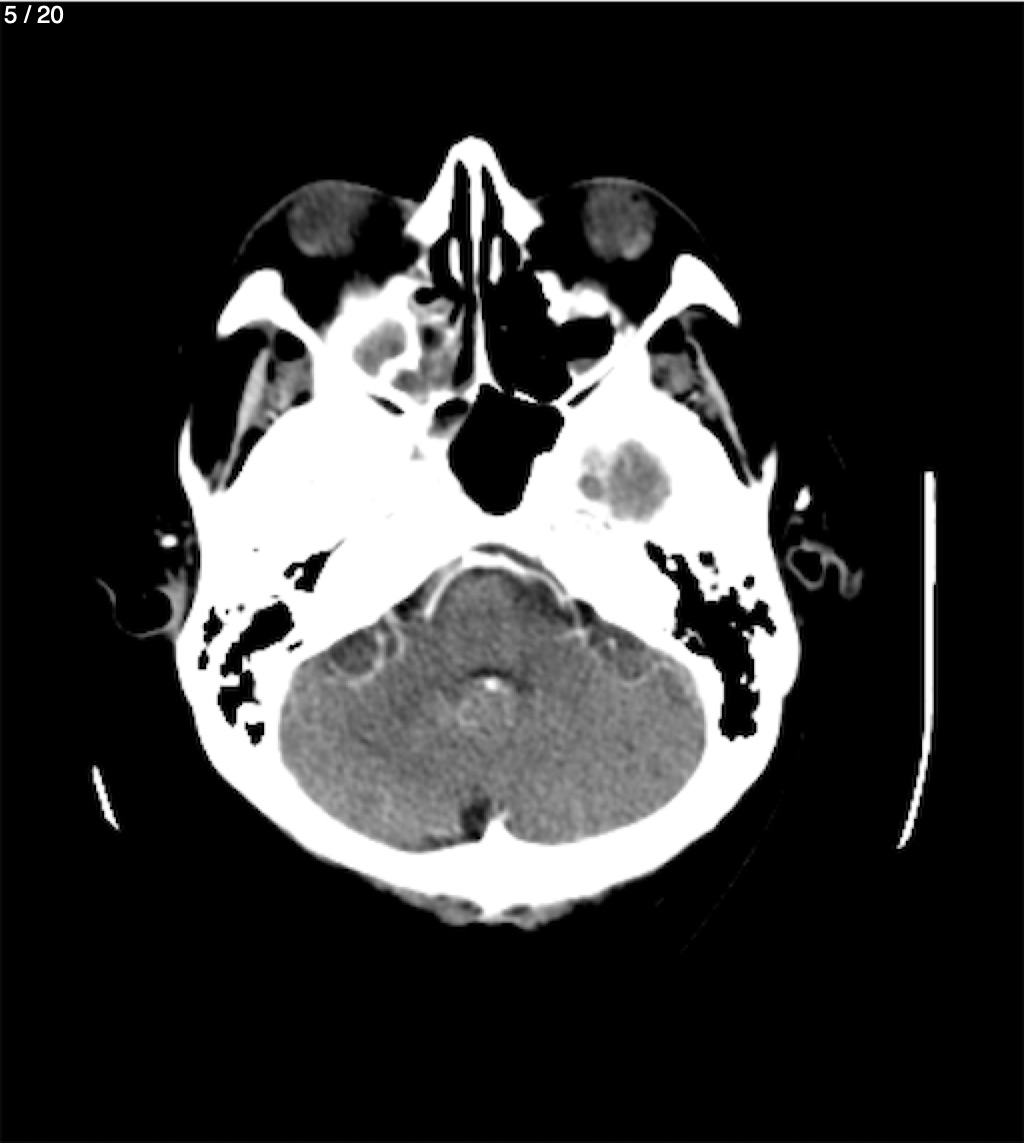

Jose Sosa Martinez 66A - Angiotac Craneo